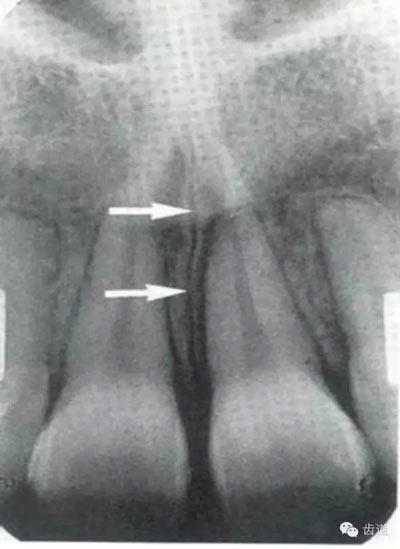

位于兩側(cè)中切牙牙根之間,由牙槽突向上,呈直線狀密度低的影像。其兩側(cè)為密度高的影像,為兩側(cè)上頜骨腭突的致密骨層。

鼻腔位于上切牙根尖的上方,顯示為對稱性半圓形密度低的影像,其中間被一密度高的骨隔分開為鼻中隔